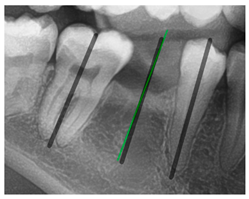

The angle bisector of the two auxiliary lines was then calculated using the angle bisector formula shown in (8), where (, , ) and (, , ) represent the coefficients of the two lines. The resulting internal angle bisector defines the preliminary implant pathway orientation derived by this framework. This bisector represents the most stable implant pathway orientation direction, ensuring that the implant avoids adjacent teeth and critical anatomical structures while maximizing bone–implant contact area. Such orientation enhances osseointegration stability and prevents complications from improper angulation, such as malocclusion or uneven stress distribution. The visualization of this process and the algorithmic design are presented in Figure 8. Finally, the auxiliary pathway generated by the algorithm was compared and overlapped with the implant pathway orientation annotated by dentists on the images to evaluate the predictive capability and accuracy of the model. The overlap results serve as a basis for further model optimization and provide valuable reference information for clinical application.

Figure 8.

Auxiliary lines are derived from adjacent teeth, the blue and yellow line is the result of implant pathway orientation visualization algorithm, and the green is the best implant pathway orientation.

3.3. Comparison with Clinical Ground Truth and AI-Assisted Framework

This subsection presents a comparison between the dentist-defined clinical gold standard and the predictions generated by our AI-assisted framework to evaluate the reliability of implant pathway orientation. The result is shown in Table 10, the preserved DPR validation set was used for verification, and the AI-assisted framework results were overlaid onto the original DPR images to provide a clear visualization. The AI-assisted framework pathways (green lines) were highly consistent with the dentists’ ground-truth annotations (black lines). Quantitatively, the mean squared error (MSE) between the predicted implant direction and the dentists’ planned results was only 1.537° across multiple test images. This minimal deviation validates the proposed system’s technical feasibility. It highlights its clinical potential to provide accurate and stable guidance for implant placement, thereby reducing the risk of misalignment and supporting efficient preoperative orientation.